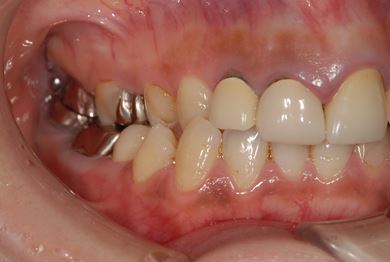

| 性別/年齢 | 女性 / 38歳 | ||||||||||||||||||||||||||||||||

| 主訴 | 奥歯の痛み(虫歯)。銀歯の所だと思います。なるべく痛くない治療がいいです。 | ||||||||||||||||||||||||||||||||

| 治療方針 | セラミック治療にて、審美的回復を行う。 | ||||||||||||||||||||||||||||||||

| 治療内容 | ハイブリッドセラミッククラウン1本(ハイブリッドセラミック用土台1本) | ||||||||||||||||||||||||||||||||

| 総治療費 | 96,600円 | ||||||||||||||||||||||||||||||||

| 治療期間 | 2ヶ月 |